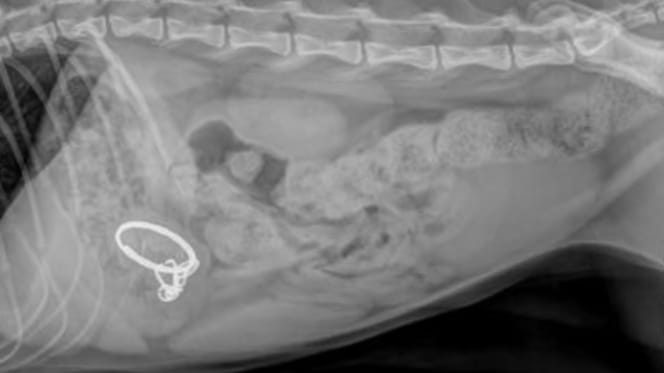

Haru the cat's X-ray

© Tierheim Duisburg / Facebook

Haru was rushed to the veterinary clinic for an X-ray.

When the vets examined the image, they turned pale. The cat's stomach contained more sharp pieces from the broken device. He was at risk of an intestinal blockage, which could lead to an agonising death.

Even more shockingly, the vets discovered that Haru must have swallowed the laser pointer before he even arrived at the shelter, which was at least ten days earlier. For ten days, he had carried these dangerous fragments inside him without a single complaint.